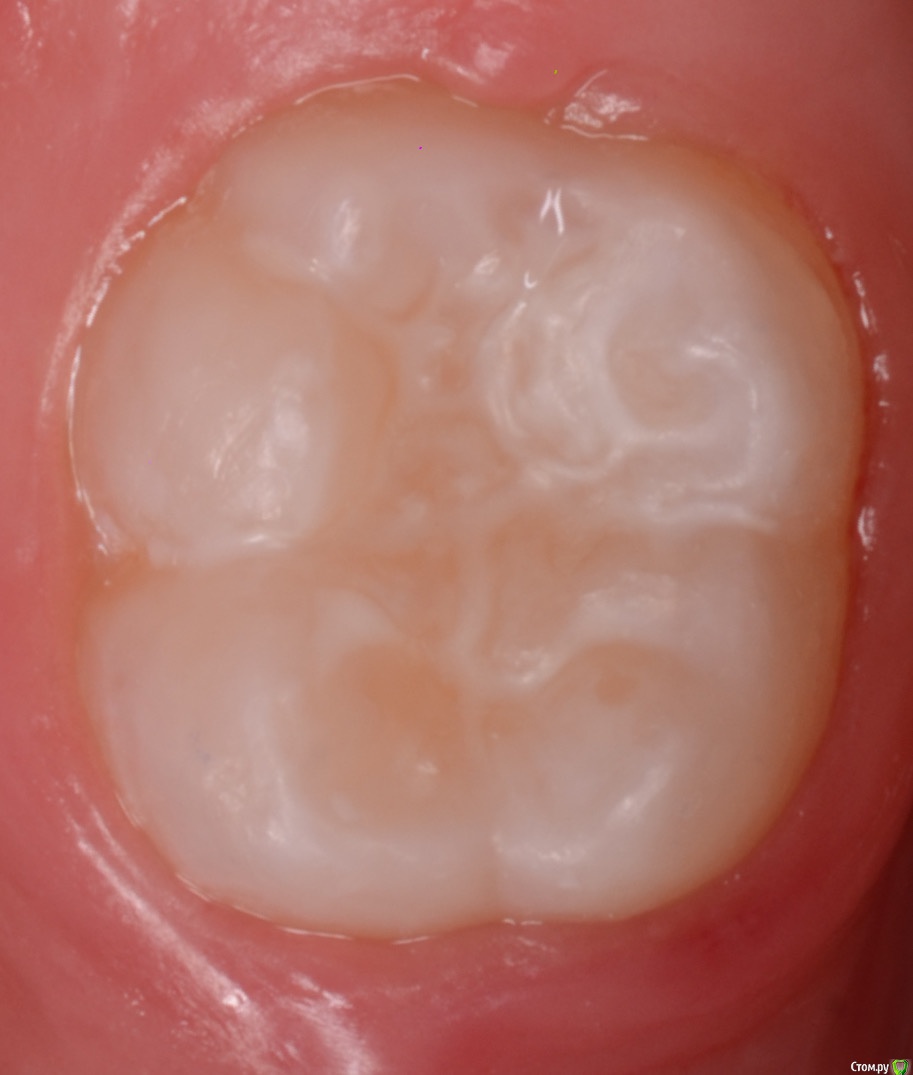

Катерина45045 Опубликовано 19 декабря, 2018 Поделиться Опубликовано 19 декабря, 2018 Решила начать лечить ампутационное в рамках ОМС.Витальная ампутация зуб 8.5. Препарирование,гемостаз,на устья ЦОЭ,прокладка фосфат-цемент,и пломба из ЭвикролаКак считаете это достойно? Не хочу делать РФ как всё,слишком много осложнений после него и ходить по 3 раза долго 1 Ссылка на комментарий

Катерина45045 Опубликовано 19 декабря, 2018 Поделиться Опубликовано 19 декабря, 2018 RG 85 1 Ссылка на комментарий

CRAZYDUCK Опубликовано 9 февраля, 2020 Автор Поделиться Опубликовано 9 февраля, 2020 Герметизация по прежнему в коффердаме . Наносим аппликационный анестетик на десну вестибулярно и язычно ( закрываю марлевым тампоном , чтобы на язык не попало . Кламп мой любимый АW dentsply ash. Он стоит крепко , не слетает . Потом платок , очистка эйрфлоу , несколько раз с контролем индикатора налёта и герметик . 3 Ссылка на комментарий